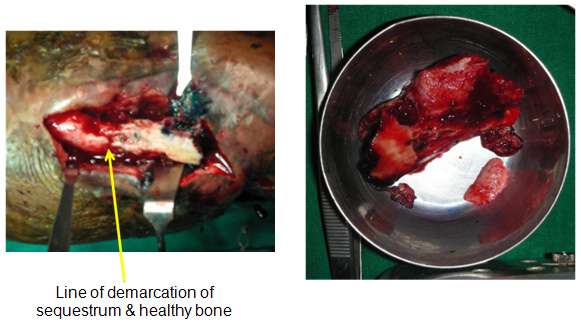

| Sequestrum â“ Dead Bone | ||

| The dead bone was excised. The line of demarcation between the dead and viable bone is shown here in the picture on the left (yellow arrow). | ||